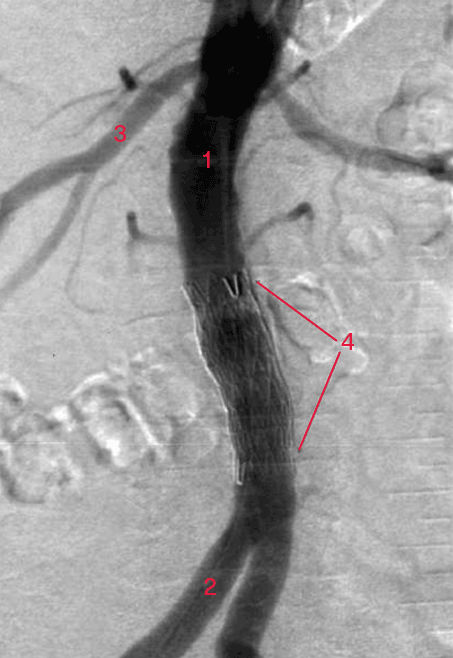

Arteriografi af aorta abdominalis efter indsættelse af aortastent indlagt via a. femoralis i lysken (røntgenkontrast-undersøgelse af legemspulsåren efter indsættelse af afstivende foring).

1. Aorta abdominalis (legemspulsåren i maven)

2. Højre a. iliaca communis (bækkenpulsåren)

3. Højre nyrearterie

4. Stent (afstivende foring for at åbne forsnævring, åreforkalkning)